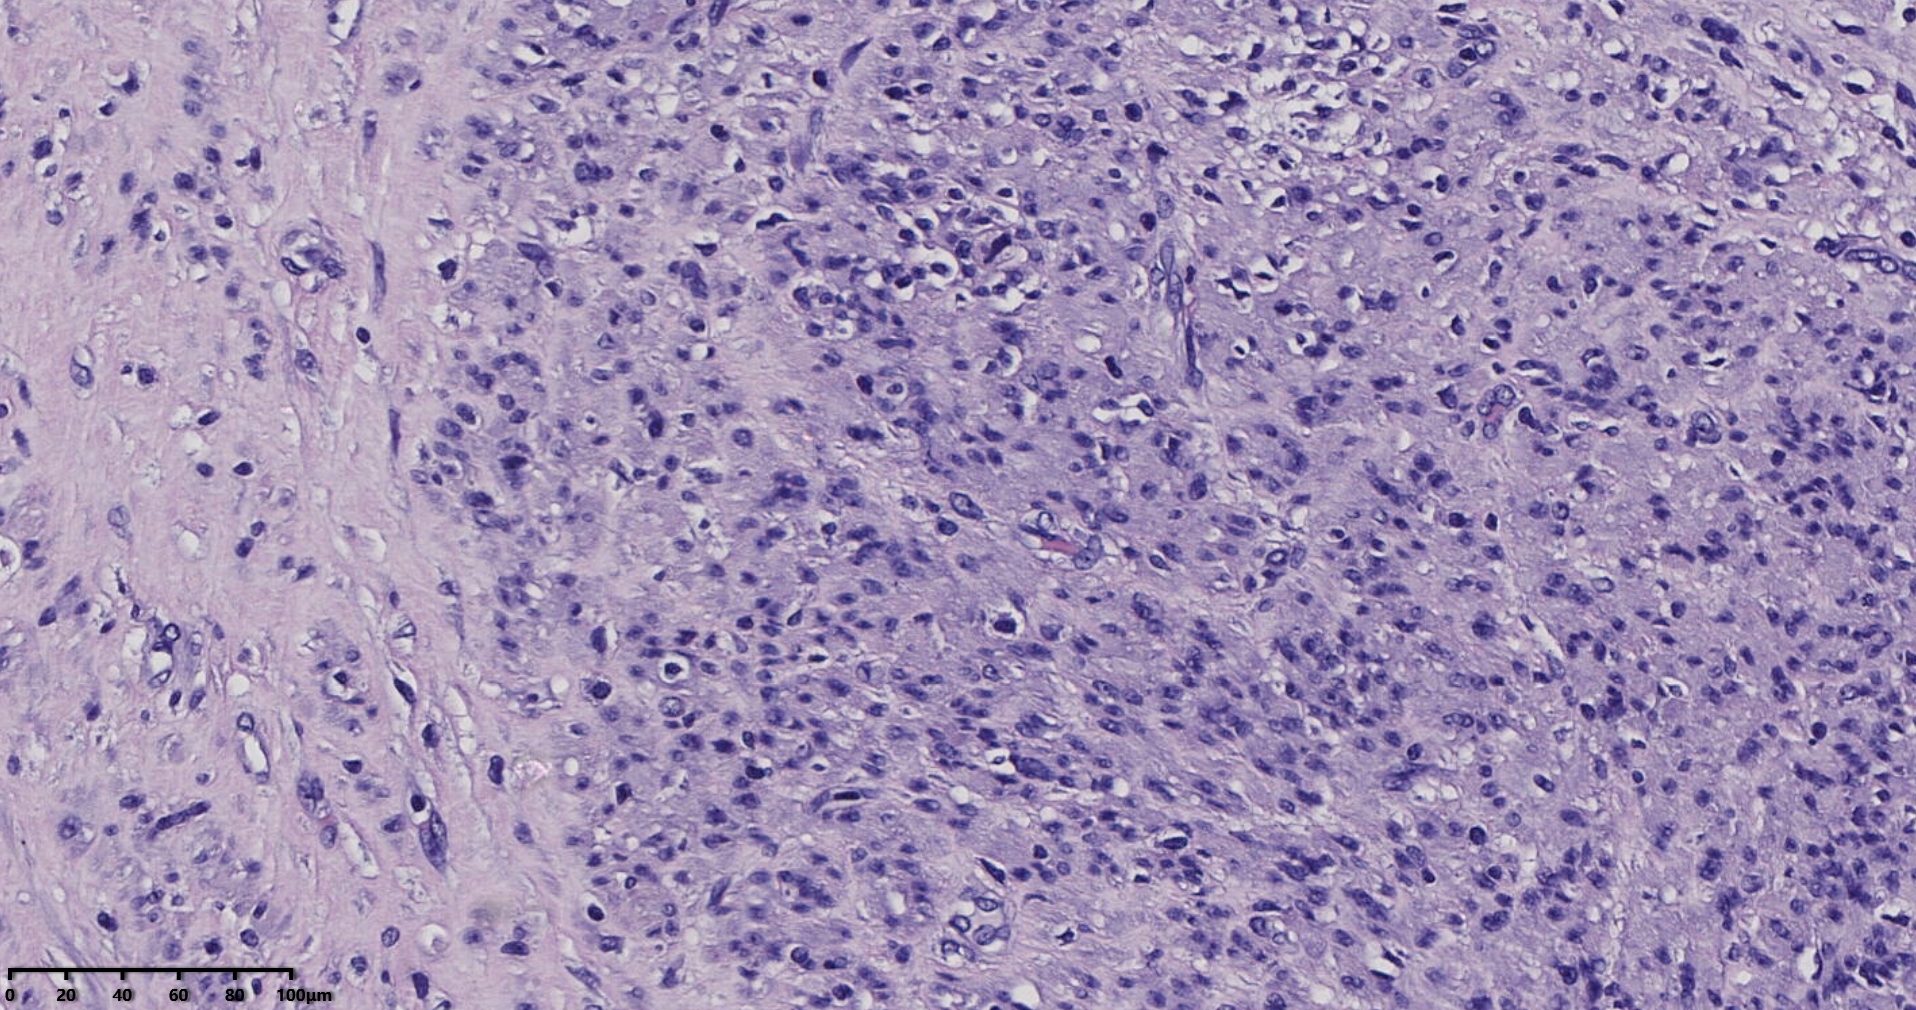

镜下所见小肿物无特殊,大肿物瘤细胞密集,中心区有变性、坏死,瘤细胞核有异型性。大肿物补充取材,发现,部分区域切面灰黄,这个区域,瘤细胞更密集,异型性更显著。肿物边缘有薄层正常平滑肌组织被覆,靠近边缘瘤细胞最密集,局部瘤组织内小血管较丰富。

会诊:考虑平滑肌肉瘤。

北医三院会诊:子宫平滑肌瘤伴红色变性可能性大,建议加做免疫组化及NGS检测进一步明确诊断。